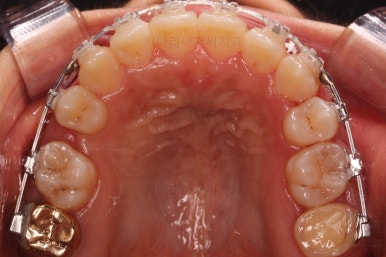

윗니만 추가적으로 발치를 1개 더 했어요.

아랫니는 최대한 추가 발치 없이 후방의 송곳니를 당겨와서 앞니 역할을 하게 했습니다.(총 4개 앞니처럼)

부분적으로 장치 셋팅을 다시 해줬고요.

밀고 당기기를 위해서 미니스크류를 셋팅했고요.

교합과 중앙선 및 디테일을 맞춰 나갑니다.

중앙선, 교합, 앞니 맞물림 등 모든 것이 좋아졌네요.

교합, 정중선 모두 좋아졌고요.